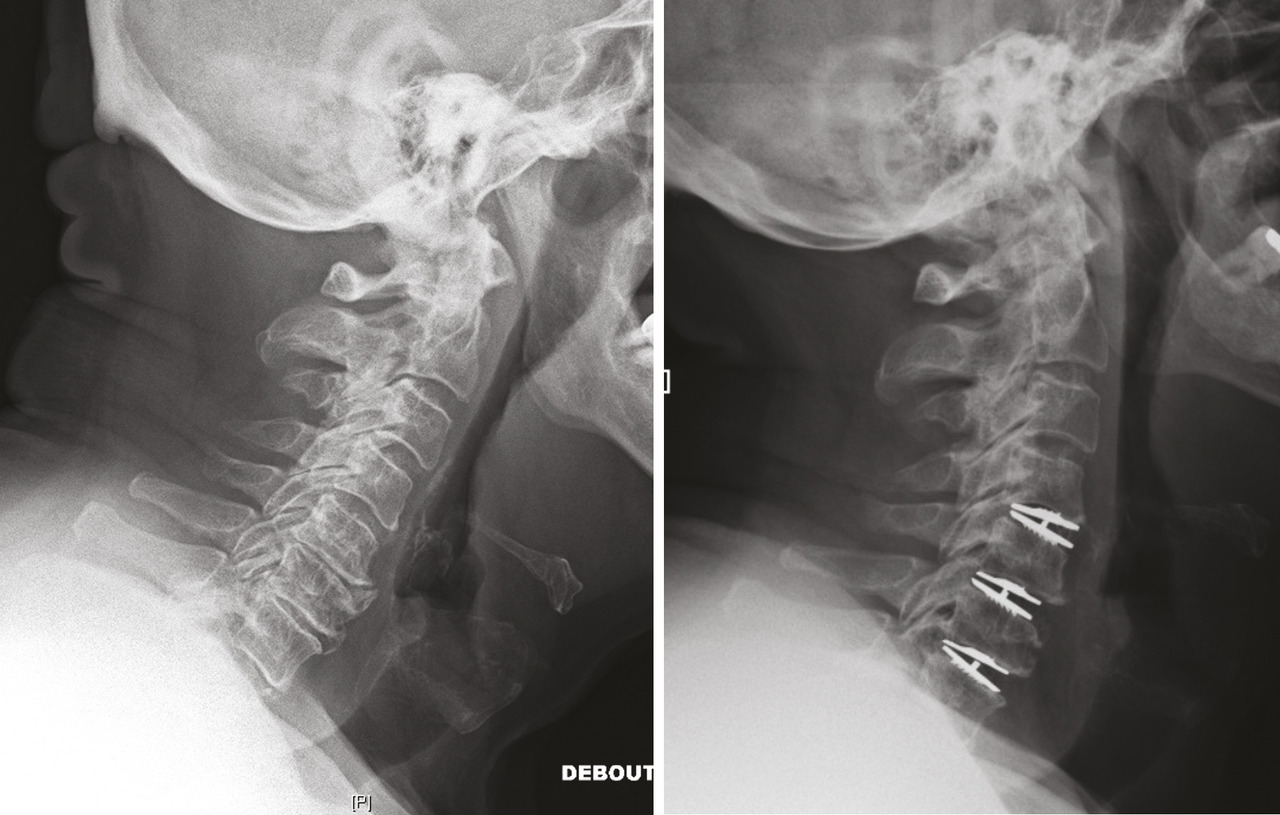

En matière de chirurgie cervicale, l’abord antérieur est préféré à l’abord postérieur car il est beaucoup plus simple et moins traumatisant. Classiquement, une arthrodèse intersomatique complétait la libération. Aujourd’hui, la tendance est à favoriser les arthroplasties discales (fig. 5 ) pour éviter toute attente postopératoire en redonnant le mouvement immédiatement.8 Plusieurs niveaux peuvent être traités en une seule chirurgie avec des suites extrêmement simples et un retour quasi immédiat à une vie normale.

En matière de chirurgie cervicale, l’abord antérieur est préféré à l’abord postérieur car il est beaucoup plus simple et moins traumatisant. Classiquement, une arthrodèse intersomatique complétait la libération. Aujourd’hui, la tendance est à favoriser les arthroplasties discales (